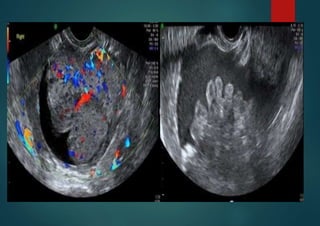

Stage 4 ovarian carcinoma with

ascites

Tumor with at least moderate blood flow, ascites, postmenopausal